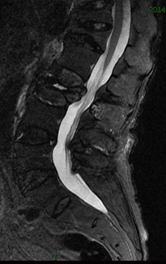

因:“腰椎骨折椎体成形术后2天”入院

患者因“脑卒中后遗症”在我中心康复治疗,于4月27日行走时滑倒腰部跌伤,当时即感疼痛,活动受限,到当地医院就诊,经CT等检查后,诊断为L3骨折,予卧床休息、口服活血化瘀及镇痛等对症治疗,患者自觉症状无改善,于6月03日在上级医院行椎体成形手术,2014年6月04日再次转入我中心继续康复治疗。患者入院时腰背部疼痛明显改善,并可下床活动。

入院诊断:(1)腰椎骨折术后